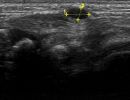

Hand Ultrasound is a simple and painless examination that does not require any preparation from the patient. Gel is applied to the patient's skin, and using a high-frequency ultrasound transducer, the radiologist conducts the examination.

During the examination, the patient remains seated and performs various hand movements as guided by the radiologist. The examination usually lasts around 30 minutes.